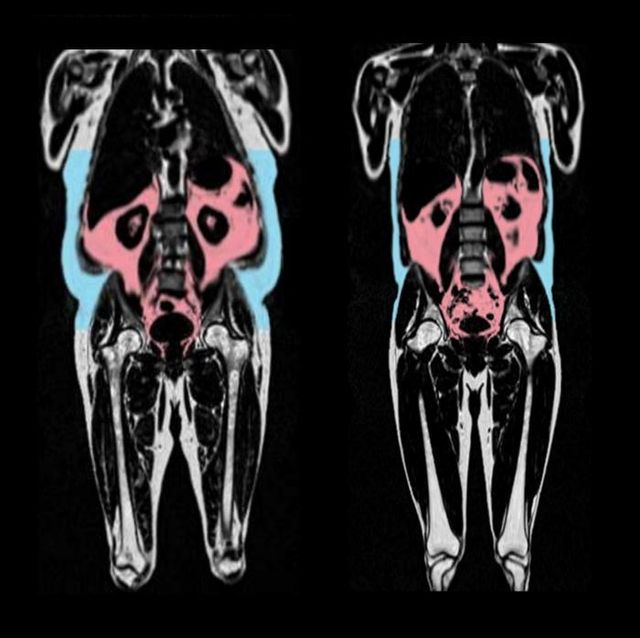

MRI 사진에서 내장지방(붉은색)과 피하지방(파란색)이 많은 사람(왼쪽)과 적은 사람의 차이가 확연히 드러나있다. [AMRA Medical 제공. 재판매 및 DB 금지]

그 결과 위, 장, 간 같은 장기 주위 복부에 쌓이는 내장지방 조직이 더 많을수록 심장 노화가 더 빨라지는 것으로 나타났다.

남녀 간 체형에 따른 차이도 확인됐다. 남자는 복부와 상체에 지방이 많은 '사과형' 체형일 경우 심장 노화가 가속되는 반면, 여성은 엉덩이·허벅지에 지방이 주로 쌓이는 '서양배형' 체형일 경우 심혈관 노화가 늦춰지는 것으로 나타났다.